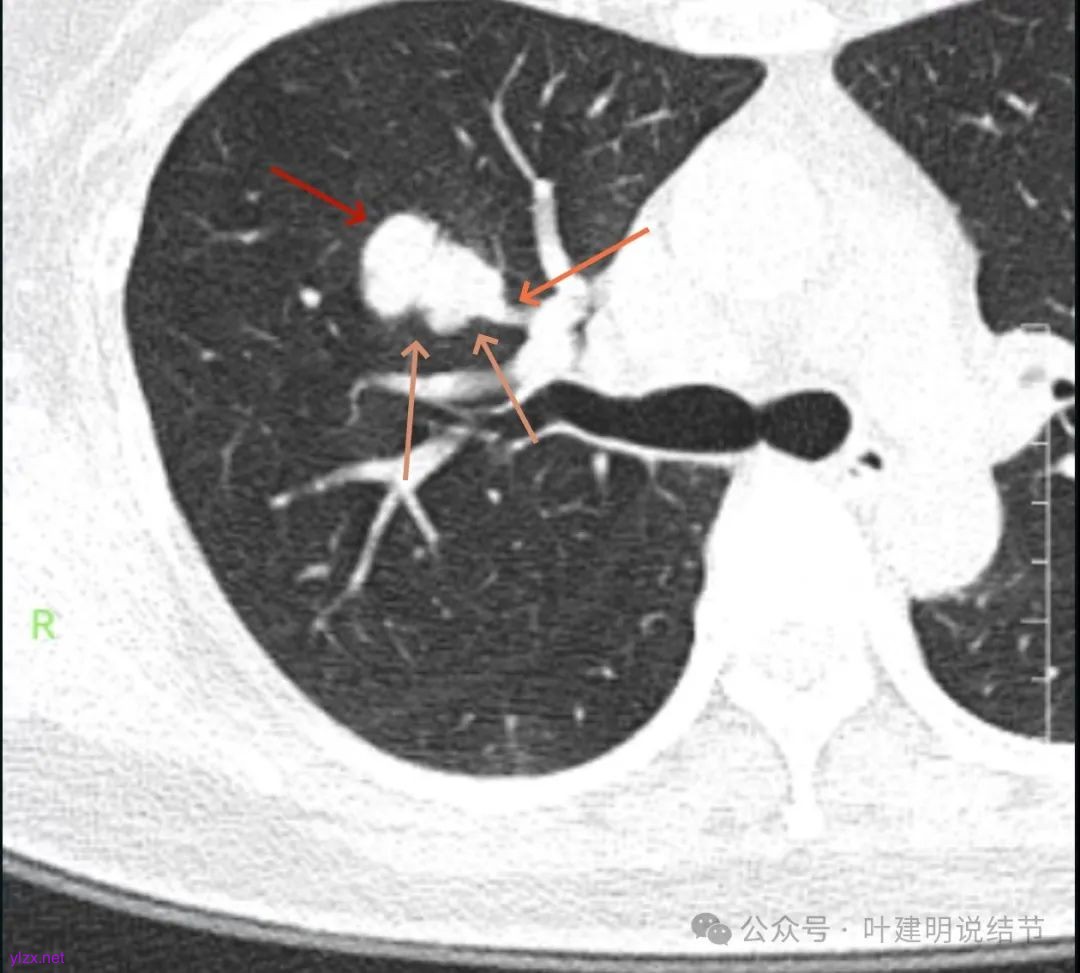

你的右上叶这个病灶基本上肯定是肺癌,要尽快处理。从影像上看有以下特点:1、整体轮廓清楚,不似普通炎症的周围有晕或阻塞性改变;2、边缘明显的浅分叶,总体上的感觉膨胀性明显,不管哪个层面看上去都是鼓鼓的;3、边缘区域有磨玻璃成分而且也是分叶状的;4、部分层面见血管进入;5、空腔病灶的壁厚薄不均,内壁不光滑。我考虑中低分化肺癌,由于腔静脉旁有明显肿大淋巴结,需要进一步完善增强CT以及PET-CT检查以明确有无远处转移,是否仍可手术治疗(从病灶本身来说是可以肺叶切除治疗的)。要尽快处理。意见供参考!